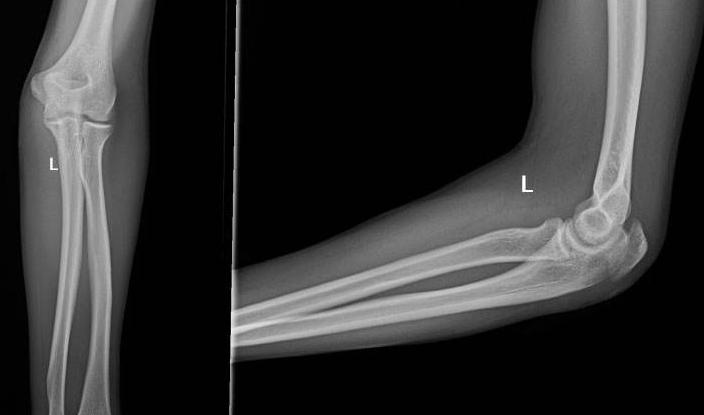

尺骨鹰嘴骨折,多发生在成年人。尺骨近端后方位于皮下的突起为鹰嘴。与前方的尺骨冠状突构成半月切迹。此切迹恰与肱骨滑车形成关节。尺肱关节只有屈伸活动,尺骨鹰嘴骨折,是波及到半月切迹的关节内骨折

尺骨鹰嘴骨折